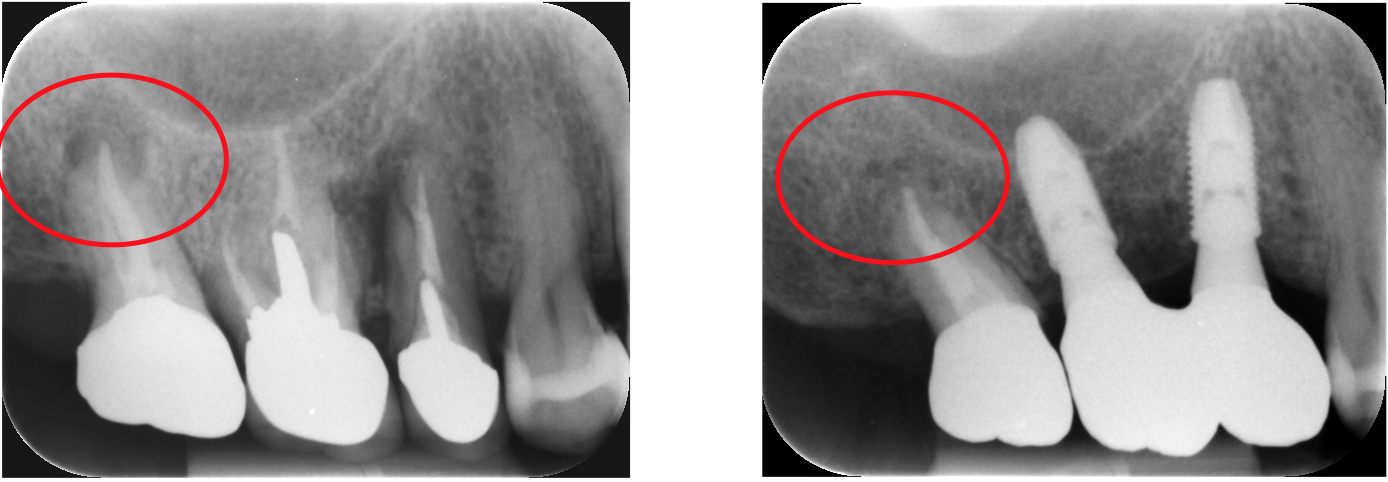

通常の根管治療を行っても症状が良くならない場合には外科的根管治療が必要となってきます。

歯根の外側に感染が及んでいる場合、通常の根管治療では感染源を除去することができないため、感染部位周辺の歯肉から感染源に直接アプローチする必要があります。

感染部周辺の歯肉を切開し、歯根の先端の病変部分を露わにします。

歯槽骨に穴を開け歯の根本から根管治療を行い、感染源を除去します

感染源を除去した後、感染している歯根の先端も取り除きます。

詰物をして歯槽骨の回復を待ち、切開部を縫合して完了です。